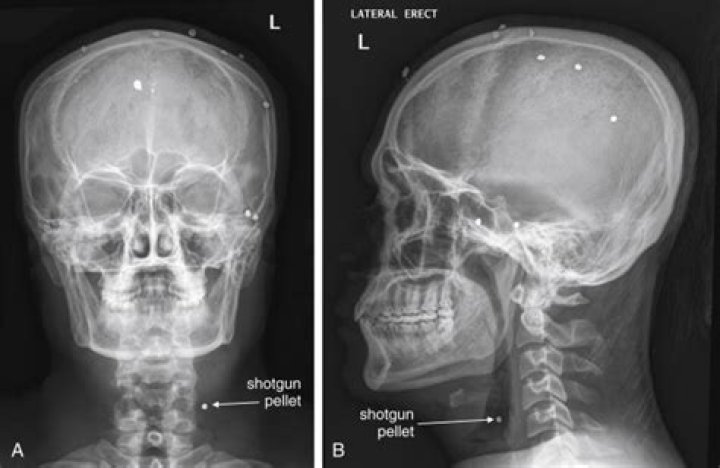

Can you see tumors on xrays?

An X-ray can detect broken bones, tumors, and even an object that is lodged inside the body. (Radiologists and technicians have found the strangest objects inside human bodies.)